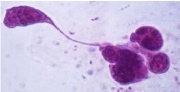

| תאריך | שם | תמונה ממוזערת | גודל | משתמש | תיאור | גרסאות |

|---|---|---|---|---|---|---|

| 05:57, 27 באוגוסט 2012 | שתן14.jpg (קובץ) | 102 קילו־בייטים | Nachi | 2 | ||

| 05:56, 27 באוגוסט 2012 | שתן13.jpg (קובץ) |  |

84 קילו־בייטים | Nachi | 2 | |

| 05:55, 27 באוגוסט 2012 | שתן12.jpg (קובץ) |  |

77 קילו־בייטים | Nachi | 2 | |

| 05:54, 27 באוגוסט 2012 | שתן11.jpg (קובץ) |  |

107 קילו־בייטים | Nachi | 2 | |

| 05:54, 27 באוגוסט 2012 | שתן10.jpg (קובץ) |  |

125 קילו־בייטים | Nachi | 2 | |

| 05:53, 27 באוגוסט 2012 | שתן9.jpg (קובץ) |  |

113 קילו־בייטים | Nachi | 2 | |

| 05:52, 27 באוגוסט 2012 | שתן8.jpg (קובץ) |  |

70 קילו־בייטים | Nachi | 2 | |

| 05:52, 27 באוגוסט 2012 | שתן7.jpg (קובץ) |  |

91 קילו־בייטים | Nachi | 2 | |

| 05:51, 27 באוגוסט 2012 | שתן6.jpg (קובץ) |  |

66 קילו־בייטים | Nachi | 2 | |

| 05:50, 27 באוגוסט 2012 | שתן5.jpg (קובץ) |  |

49 קילו־בייטים | Nachi | 2 | |

| 05:49, 27 באוגוסט 2012 | שתן4.jpg (קובץ) | 102 קילו־בייטים | Nachi | 2 | ||

| 05:49, 27 באוגוסט 2012 | שתן3.jpg (קובץ) |  |

67 קילו־בייטים | Nachi | 3 | |

| 05:47, 27 באוגוסט 2012 | שתן2.jpg (קובץ) |  |

43 קילו־בייטים | Nachi | 3 | |

| 05:46, 27 באוגוסט 2012 | שתן1.jpg (קובץ) |  |

106 קילו־בייטים | Nachi | 2 | |